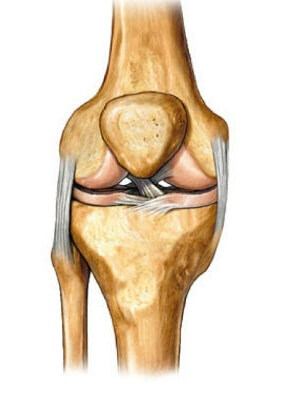

Кости, образующие коленный сустав, не соприкасаются, так как между ними расположена особая прокладка. Именно благодаря менискам все движения в колене происходят плавно без рывков и боли. Обеспечивают амортизационный эффект два мениска – латеральный и медиальный, которые имеют вид полумесяцев и удерживаются в полости сустава связками. Однако чрезмерное давление на суставные элементы, неестественные движения и удары могут спровоцировать повреждение мениска коленного сустава.

Болезнь классифицируется по виду повреждения и месторасположению менисков.

При повреждении мениска с наружной стороныставится диагноз латеральная менископатия, что встречается в 21% случаев.

Внутренний же или медиальный хрящ чаще подвергается травмированию, что подтверждается в 75%. Встречаются и двусторонние повреждения менисков колена.